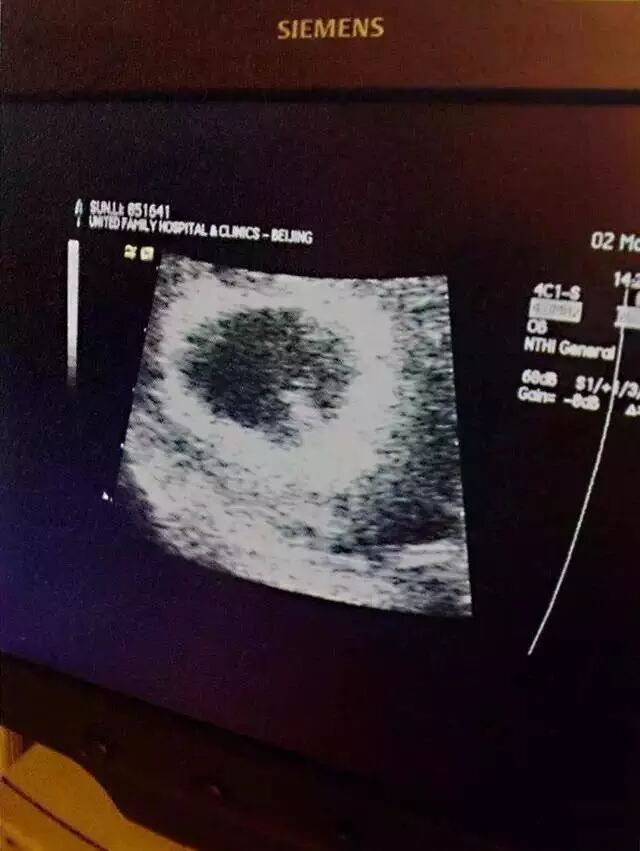

“2013年12月,妹妹降生,从那一刻起,我们踏上新旅程。从此,我们一家四口啦!”

▲妹妹